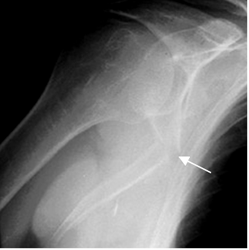

Fig 58. Fractura de escápula.

Rx oblicua de hombro. Fractura angulada del tercio medio de la escápula.